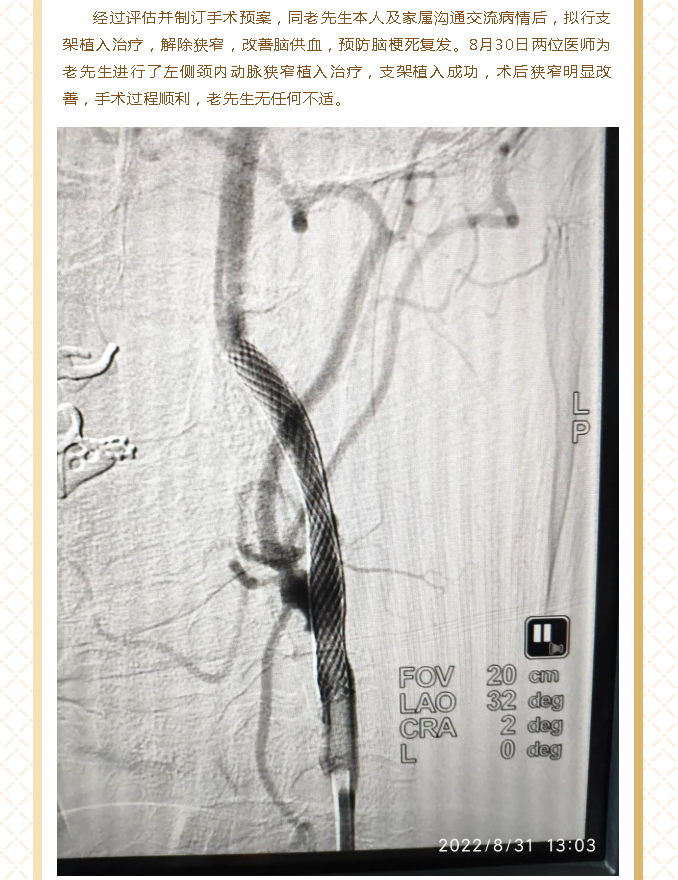

北医三院机场院区导管室顺利开展首例脑血管造影及颈动脉狭窄支架植入术